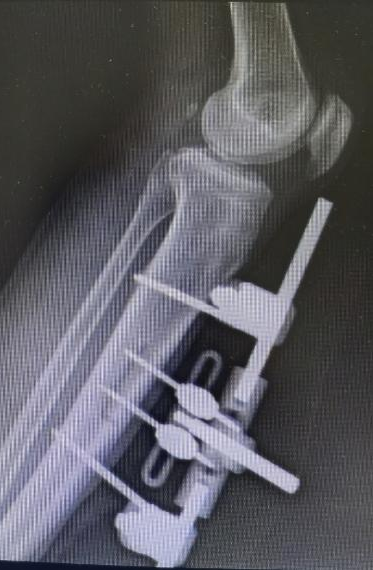

王瑞良主任團隊經(jīng)過詳細檢查發(fā)現(xiàn),患者足底軟組織大面積壞死,深部肌腱、骨質(zhì)外露,合并嚴重感染。"當(dāng)時患者已做好截肢心理準備,但考慮到他正值壯年且還有勞動需要,我們?yōu)槠涮魬?zhàn)保肢治療。"王主任介紹,目前其手足顯微外科開展"脛骨橫向骨搬運術(shù)"已非常成熟,已成功為數(shù)十位患者“保肢”,該項技術(shù)通過精確調(diào)控骨骼微動刺激血管神經(jīng)再生,且創(chuàng)傷小、恢復(fù)快,可以有效解決糖尿病足、下肢動脈硬化閉塞癥的治療難題。術(shù)后張先生肢體血運恢復(fù)良好,妻子紅著眼眶回憶:"真的沒想到可以保住他的腳,看著他的腳一天天變好,就像看到一家人希望。"

△脛骨搬運術(shù)前術(shù)后CTA血管對比,血管再生良好